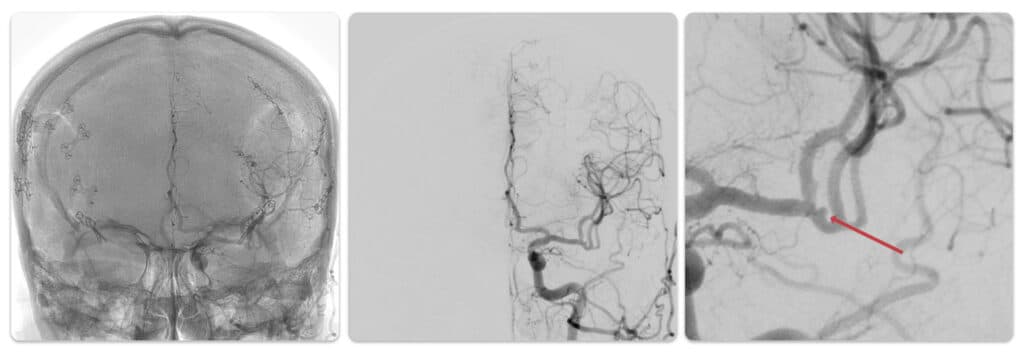

Angiografia com subtração digital

Como já vimos, a angiografia usa raios-X. Mas você deve lembrar que o raio-X mostra muito bem os ossos. Isso quer dizer que a presença dos ossos e outros artefatos pode atrapalhar a visualização correta dos vasos sanguíneos.

Por isso, usamos uma técnica chamada de subtração digital, que consiste no seguinte: uma imagem inicial é feita, mostrando os ossos, como em uma radiografia convencional. Após isso, por técnica digital, essa imagem inicial é subtraída das imagens seguintes, deixando apenas o que muda em relação a elas, ou seja, o contraste com sangue dentro dos vasos sanguíneos.

As imagem abaixo mostram esse processo.

À esquerda, vemos uma angiografia sem subtração, com os ossos, vasos sanguíneos e clipes metálicos que ficaram depois de uma clipagem de aneurisma. Na imagem do centro, temos a imagem subtraída, em que vemos apenas os vasos. Na direita, identificamos um pequeno aneurisma residual após clipagem.